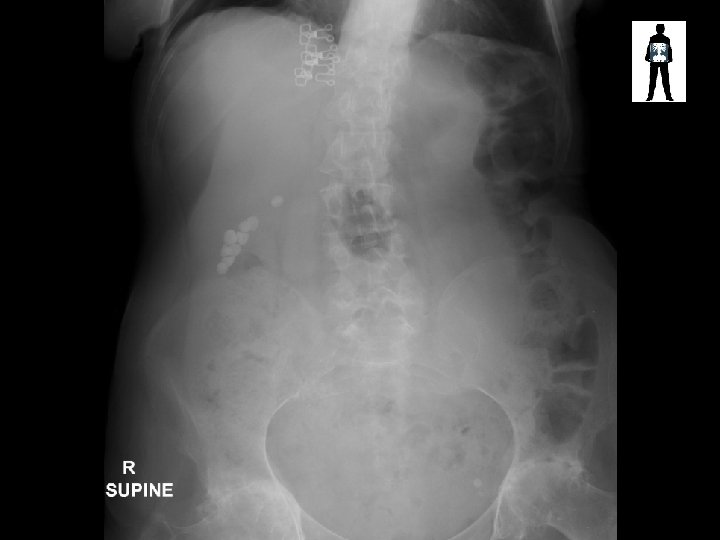

Bra artefact Calcified gallstones Phlebolith in bladder

Air in stomach STAGHORN CALCULUS Complete obstruction of the renal pelvis Bladder phlebolith